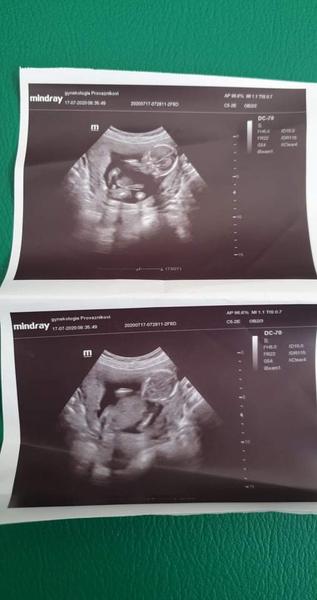

@allisenka no vim o čem mluvíš doma mam 9 let syna , pak 21nesicu syna a muz ma 5 let syna ted jsem v 18+5tt a přiložit foto cca ze 13tt a potom 15+6 . Foto ze 13tt tak me 76holek vi maminek reklo ze vidi holku kávové zrno a to tam vidím i ja a v 15+6tt me doktor rekl ze asi kluk a pritom u synu jsem jedla palive slané nevolnost jsem mela ze hrůza a ted jim sladké maso nemohu ani cítit a vse nasvědčuje na holcicku ale to co me doktor ukazuje na utz v 15+6 tt si myslíme ze je zkroucena noha pac takhle velký pindik neni možná okolo 20 tt😅🤣

@rennye spis me zajímá co si myslíte o te první fotce jak si doktor myslí že je to pindik nebo vam to taky neprijde spis jak ztocena noha

@almidrob2539 Pindík to není 😉

@rennye 😅🤣 at je to klidně kluk ale kdyz doktor rekne ze noha je pindik a ke všemu v 15+6tt a takhle veliký tak co me řekne na další kontrole to uz to bude mít jak slon 🤣😂🤣

@almidrob2539 mě se to taky nějak nezdá.. Že by mu levitoval ve vzduchu? 😃 Z té fotky to fakt nejde poznat. Ale je pravda, že u kluků jsem sama koukala, jake to je velké, když jsou takoví prtavi 😃